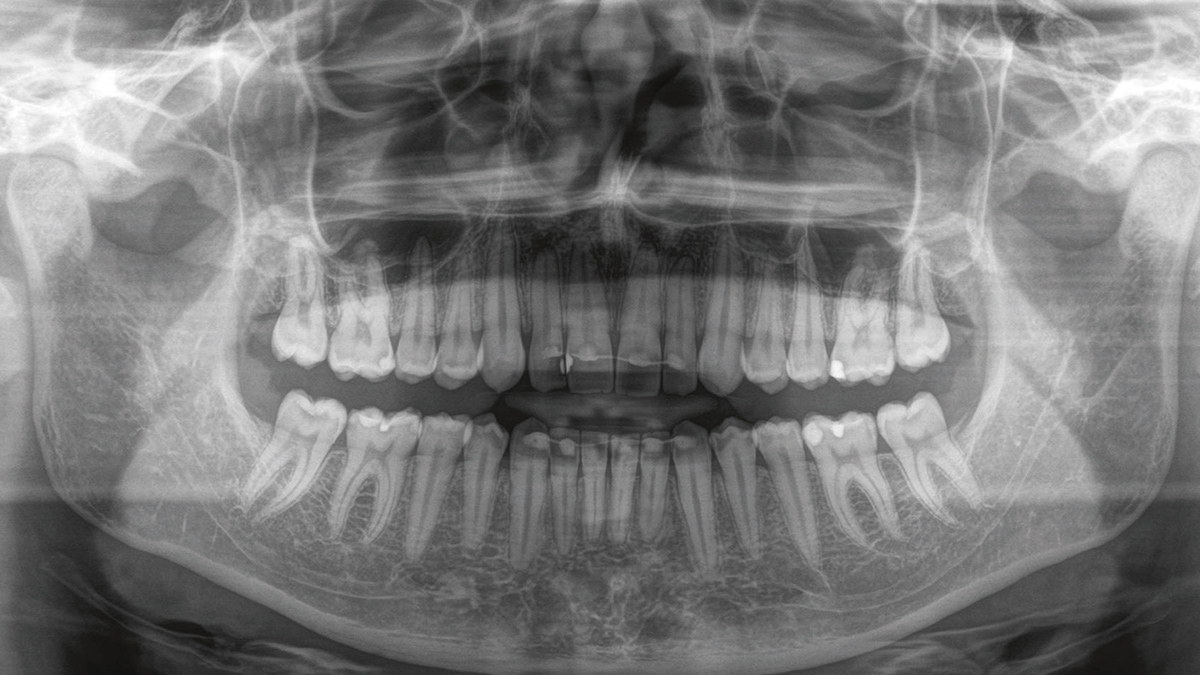

Panorama-Röntgenbild des gesamten Gebisses

Ob wir nun den Zustand Ihrer Füllung überprüfen wollen, den Verlauf einer Zahnwurzel nachvollziehen möchten oder Ihren Zahnersatz ideal planen wollen: Digitale Röntgenaufnahmen von Zahn und Kiefer sind unverzichtbar für eine exakte Diagnostik und legen somit den Grundstein für eine erfolgreiche Behandlung. Auch Entzündungsherde und Karies können wir somit frühzeitig erkennen. Denn nur durch das Röntgen werden auch von außen nicht erkennbare Details sichtbar. Somit erhalten wir ein verlässliches Bild über Ihren Zahnzustand.

Digitales Röntgen bietet außerdem weitere Vorteile: Durch die digitale Verarbeitung der Signale sind höhere Auflösungen und auch Aufnahmen im Mikrometer-Bereich möglich, zum Beispiel im Zahnwurzelkanal. Zudem können wir damit auch Farb- und sogar 3D-Aufnahmen von Kiefer und Zähnen anfertigen. Diese räumlichen Aufnahmen bringen auch kleinste Details ans Tageslicht und ermöglichen uns somit eine deutlich präzisere Diagnostik.